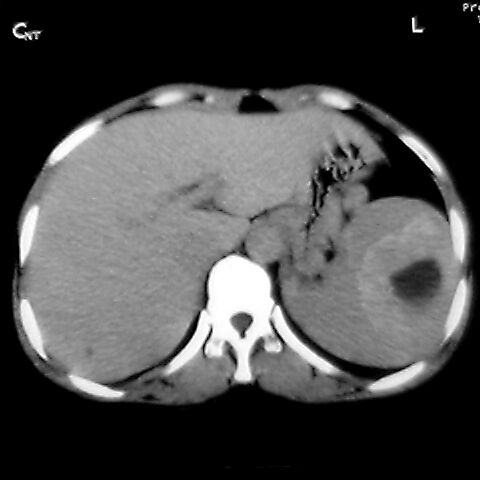

女 48岁 食道癌术前体检发现脾占位。

脾胀内部巨大低密度肿块,边界清或不清,中心坏死,轻度增强,内见散在钙化,结合食道癌病史多考虑:转移癌.

脾脏低密度灶伴钙化,增强化明显,中心见液化坏死灶,强化延时明显。考虑血管瘤。转移瘤待排。